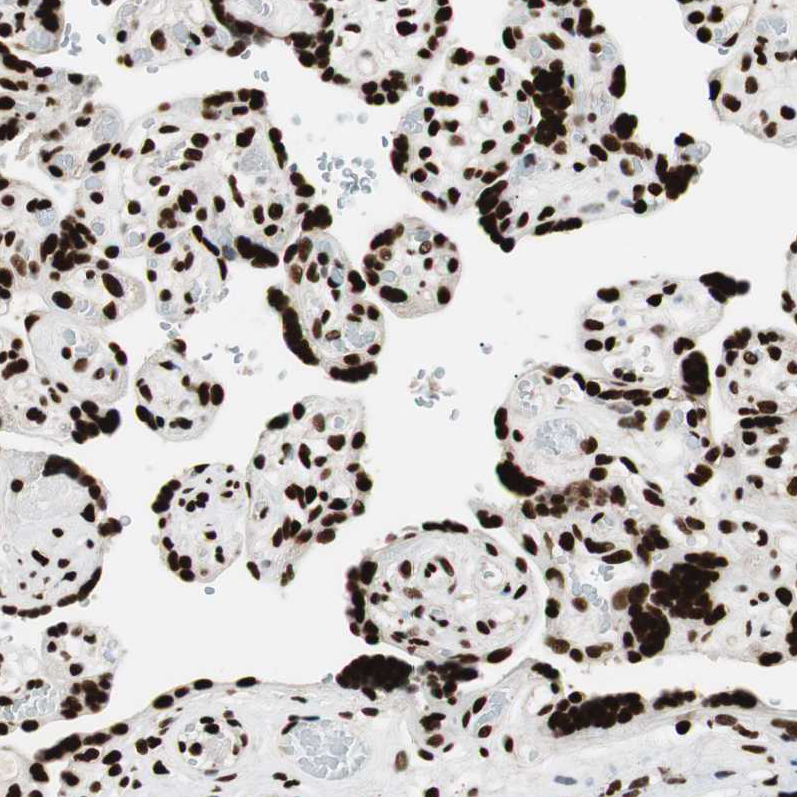

Immunohistochemical staining of human placenta shows strong nuclear positivity in trophoblastic cells.